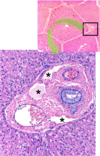

Explain the image

Lower panel is a higher magnification of the portal area where the branches of the hepatic artery, hepatic portal vein, and the bile duct are visible. Space of Mall is indicated by the asterisks.

- 6.1